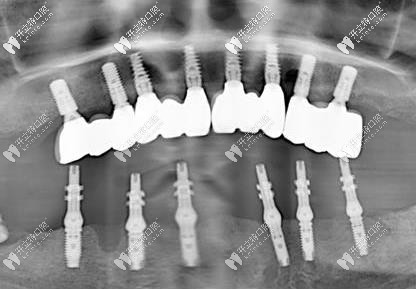

這次種牙僅僅植入了六顆植體,好像是什么ALL-on-6技術(shù),只需要六顆種植體,然后做成一個(gè)連橋冠還是什么就可以了。還真別說,這個(gè)技術(shù)真厲害啊,六顆植體價(jià)格也沒有之前的做著貴,價(jià)格方面我也是比較能接受的。

這是種完牙后的照片

讓我稱贊的是這個(gè)當(dāng)天種完牙后,效果也是比較不錯(cuò)的,雖然醫(yī)生說可以吃一些較軟的食物,但是我還是擔(dān)心,就沒吃,第二天才開始吃的東西,也沒啥太多不舒服的感覺。

種植牙后的樣子

不知道大家看了我做的半口種植牙效果圖咋樣,我個(gè)人還是非常認(rèn)可這個(gè)技術(shù)的,畢竟不用等那么久,中間的艱辛也不用等啦!